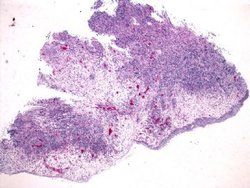

(2)骨髓象:骨髓增生活躍,粒系增生活躍,粒系早幼粒、中幼粒、晚幼粒、桿狀核、分葉核階段均可發現嗜酸粒細胞。